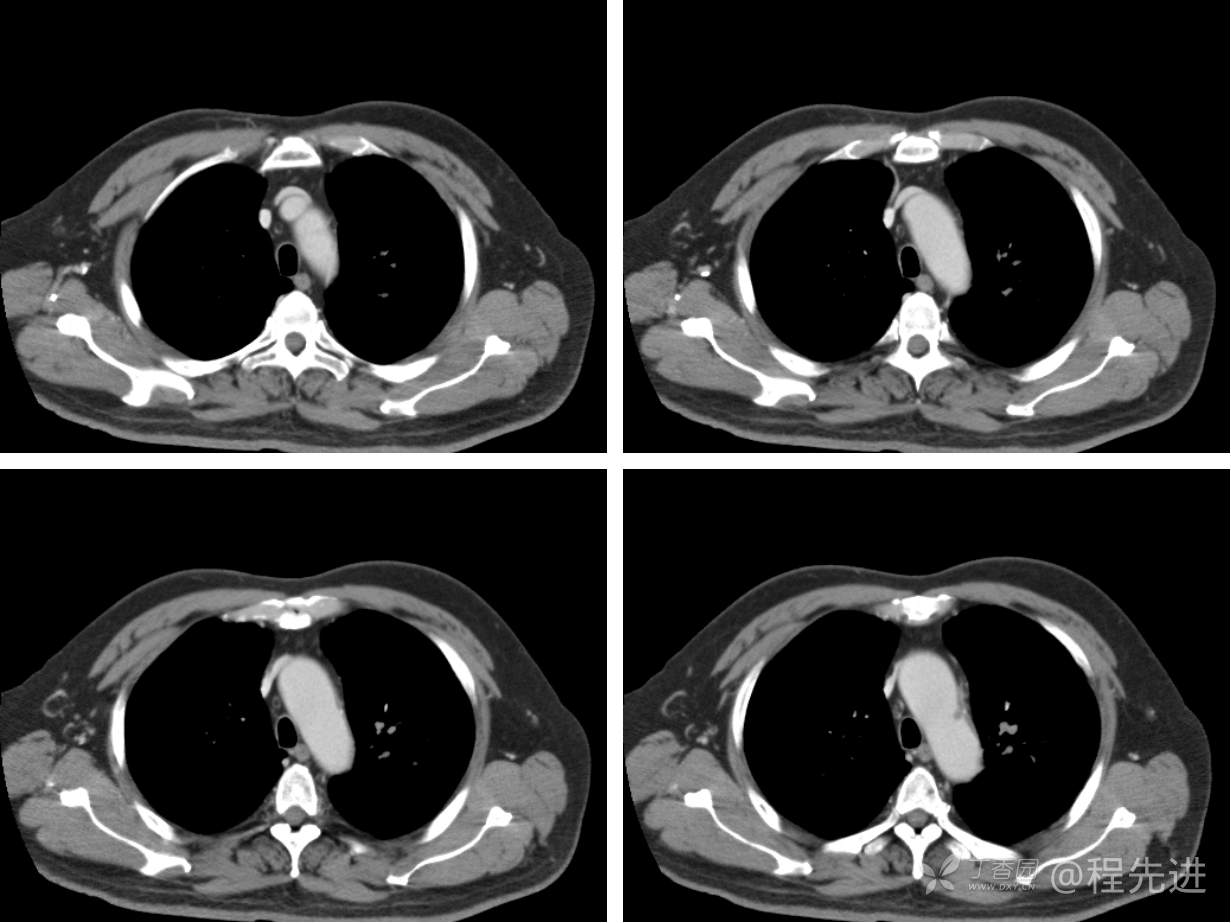

现病史概要:患者入院前约半月无明显诱因下出现咳嗽、胸闷症状,无明显发热症状,咳少量白痰,无明显咯血、喘息、头晕等不适,就诊我院查胸部CT示上纵膈肿物,左肺上叶支气管内肿物,现为行进一步治疗收入胸外科,患者近来饮食睡眠尚可,二便如常。